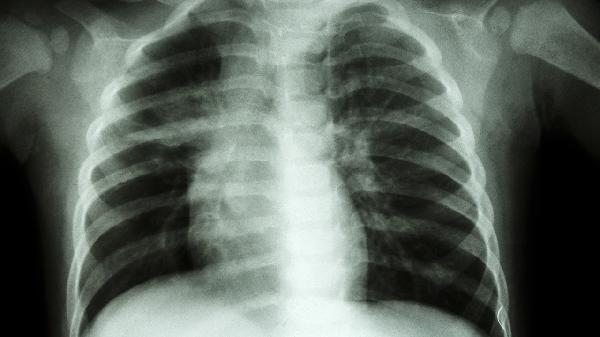

两种畸形均可通过体格检查初步判断,但确诊需结合胸部X线或CT三维重建。鸡胸患者胸骨角增大、肋软骨过度生长在影像学上表现明显,肋骨翻转则可见肋骨下缘外翻的典型特征。非手术治疗如矫形支具对生长发育期患者可能有效,骨骼成熟后严重畸形需考虑手术矫正。鸡胸常用改良Ravitch手术或微创Nuss手术,肋骨翻转则需个性化设计截骨方案。